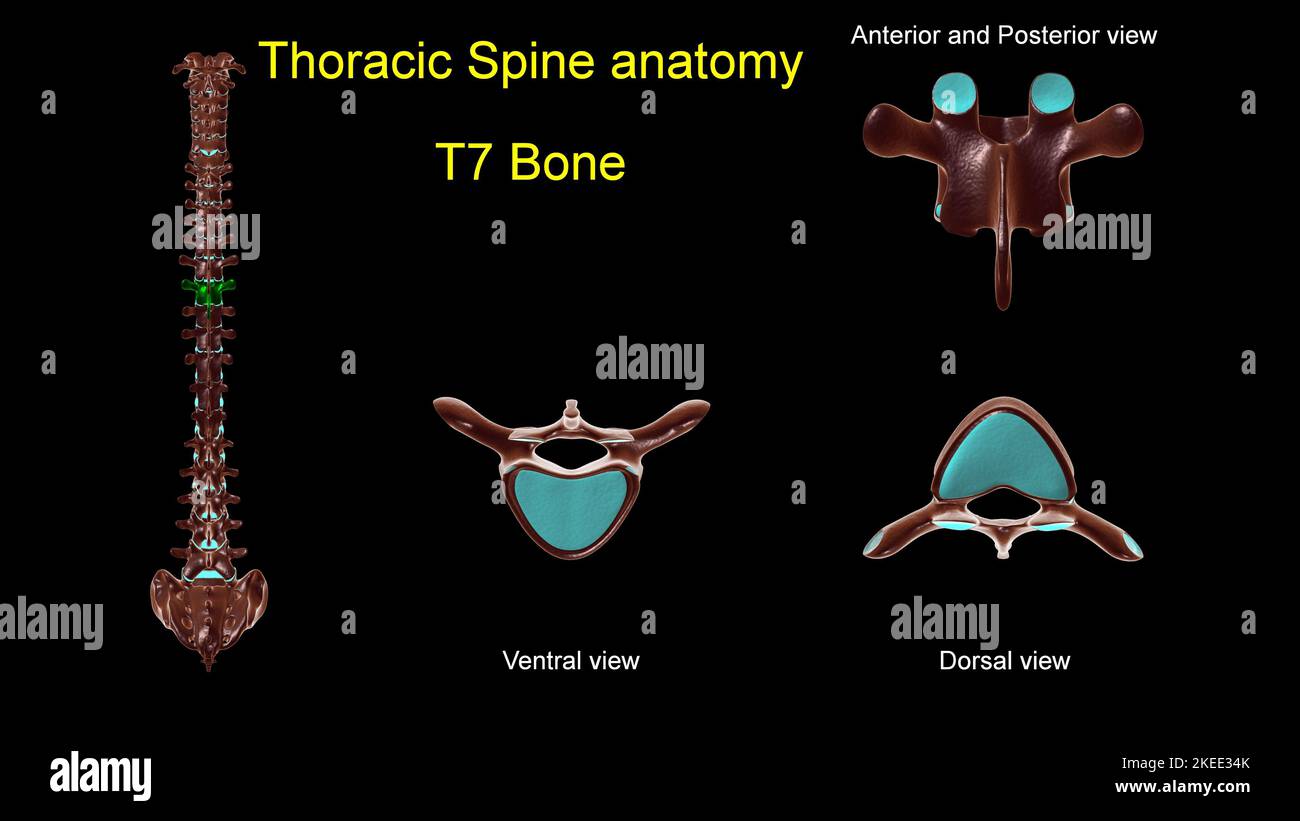

RF2KEE32B–Colonna toracica T 1 anatomia ossea per concetto medico 3D Illustrazione con vista anteriore e posteriore

RF2KEE329–Colonna toracica T 11 anatomia ossea per concetto medico 3D Illustrazione con vista anteriore e posteriore

RF2KEE342–Colonna toracica T 3 anatomia ossea per concetto medico 3D Illustrazione con vista anteriore e posteriore

RF2KEE326–Colonna toracica T 4 anatomia ossea per concetto medico 3D Illustrazione con vista anteriore e posteriore

RF2KEE34K–Colonna toracica T 7 anatomia ossea per concetto medico 3D Illustrazione con vista anteriore e posteriore

RF2KEE333–Colonna toracica T 6 anatomia ossea per concetto medico 3D Illustrazione con vista anteriore e posteriore